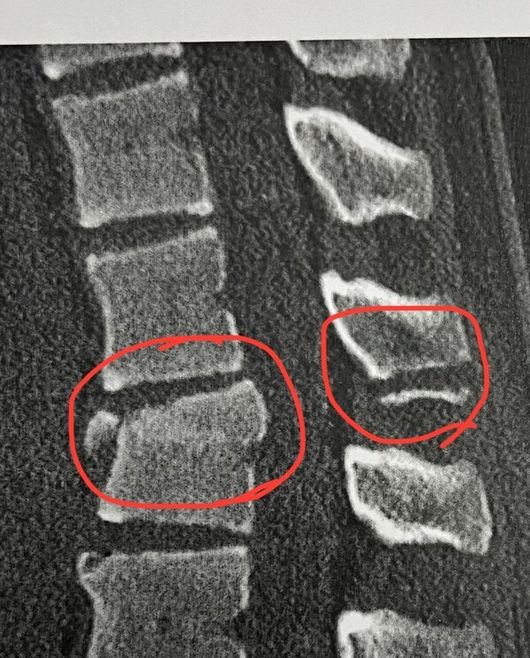

이어 "불과 2년 전, 15살 때 락스에서 스노보드 인생을 끝낼 수도 있었던 큰 부상을 겪었다. 현지에서 척추 압박골절로 긴급 유합 수술을 받았고, 다시는 스노보드를 할 수 없을 것이라는 이야기를 들었다"라며 "열흘 뒤 세균 감염으로 긴급 입원하게 됐다. 염증 제거를 위한 2차 수술과 척추뼈에 골반뼈를 이식하는 3차 수술까지 이어졌다"고 설명했다.

고통은 거기서 끝나지 않았다. "한 달간의 입원과 집중적인 항생제 치료를 거치는 동안 두려움과 우울함도 함께 이겨내야 했다"라며 "재활을 통해 다시 보드에 서기까지 1년이 걸렸다. 그래서 이번 시즌이 더욱 감격스럽고 특별하게 느껴진다. 그때 포기하지 않았던 자신이 자랑스럽다. 부상에 대해 다시 이야기하고 싶지 않았지만, 많은 분이 요청해 주셔서 이렇게 남기게 됐다"고 덧붙였다.

[사진] 최가온 SNS 캡처.